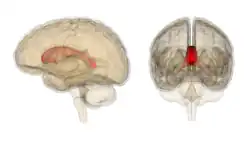

Die Mild Encephalopathy with Reversible Lesion in the Splenium (MERS) ist eine auf das Hinterende (Splenium) des Balkens beschränkte Enzephalopathie, die meist im Zusammenhang mit Infektionen auftritt.